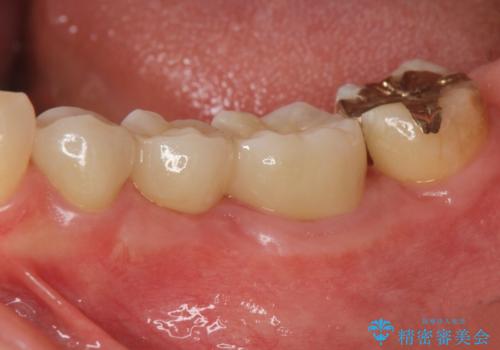

親知らずのせいで隣の歯が虫歯に 40代男性

歯並びや奥歯の痛み 色々と治したい 総合歯科診療

インプラント治療・セラミック治療を含む 全顎的虫歯治療

担当医 大元洋佑